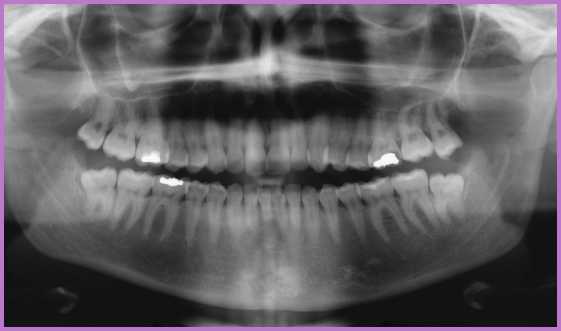

A panorámaröntgenek (rövidítve OP) 2 dimenziós képet mutatnak a csontállományról (lásd a képet).

Ez jó áttekintő képet ad a kezelőorvosnak, viszont a felvétel a különböző pontokon eltérő mértékben torzít.

Ezzel szemben a CBCT (Cone Beam CT)-felvétel 3 dimenzióban mutatja meg a csontszövet szerkezetét, mégpedig torzulások nélkül. Tökéletesen láthatóak az anatómiai képletek, a bölcsességfogak arcüregtől vagy idegcsatornától való távolságáról, egy ciszta pontos kiterjedéséről pontos információt nyújt a kezelőorvosnak. Továbbá arról is, hogy az implantátum tervezett helyén megfelelő-e a csontállomány, mivel a csont szélessége és magassága is pontosan lemérhető rajta.